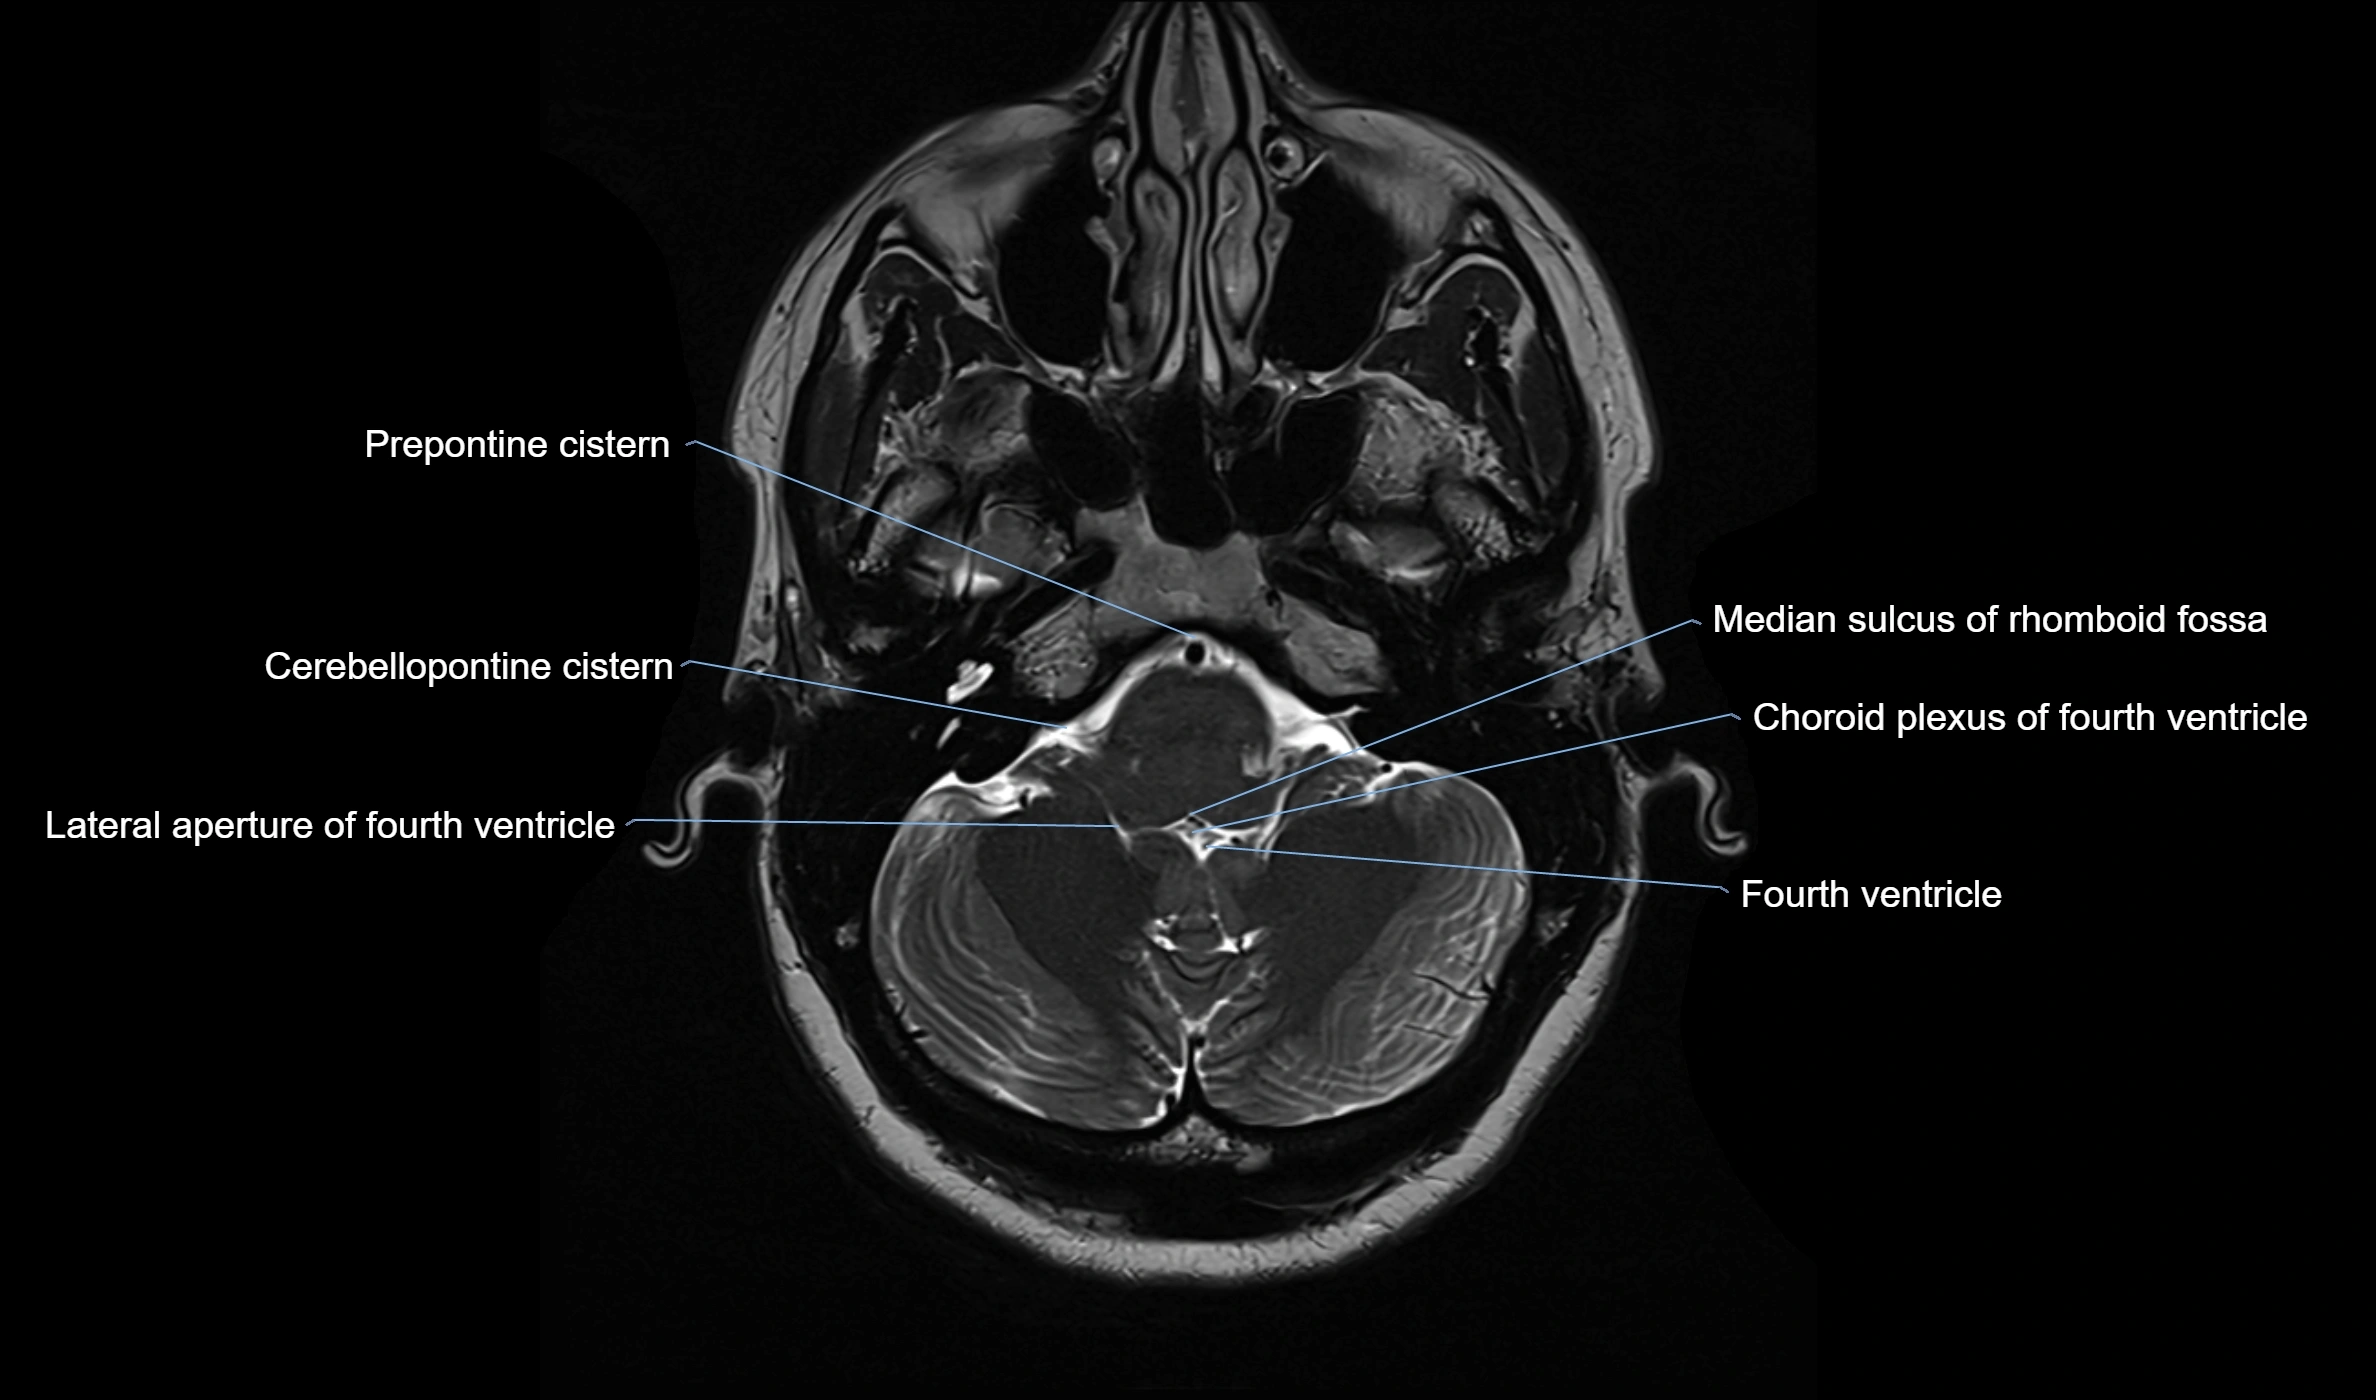

CT image

image